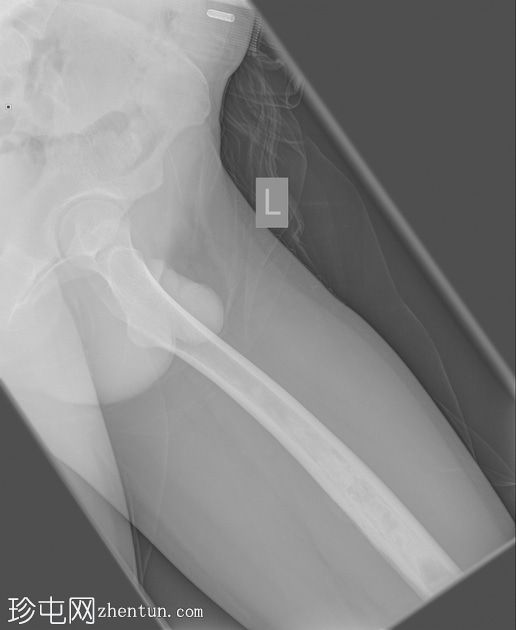

X光片

正面

侧面

斜面

左股骨中段可见边界不清的硬化区域,伴有宽阔的过渡区和虫蛀状外观。

邻近软组织可见小块钙化灶。无骨折或脱位。